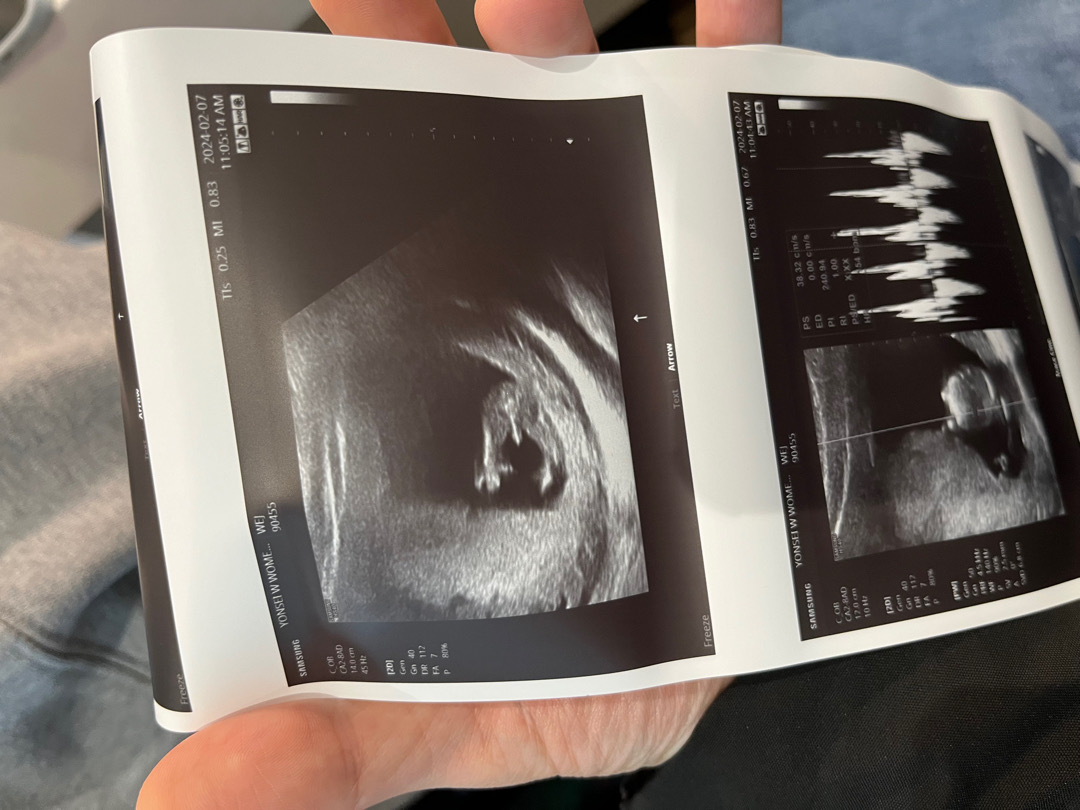

13주차 아들 아빠 확정..

13주 0일인데 오늘 너무나 선명한… 어렸을 땐 아들 낳고 싶다가 내 눈에 더 이쁠 것 같은 딸 낳고 싶다가 지금은 또 든든한 첫 아들이 오히려 좋을 것 같다 생각했는데 15, 16주나 되야 확인할 줄 알고 기대 안했는데 이렇게 알게되니 ㅎㅎ 생각보다 감동은 없었고 궁금증이 해소됐다 정도 기분이네요 ㅎㅎ 문득 다들 엄청 성별들 궁금해하시는 것 같은데 알고 난 이후 글들도 궁금하네요 건강하세요~

ㅋㅋㅋ 아니 ㅋㅋㅋ 너무 확고 하네요😆 여태봤던 각도법 미션 초음파사진중에 이런 단호박은ㅋㅋㅋ 축하드려요🎉🎉🎉 너무 선명해서 신기하네요😄

저도 병원에서 확정해서 말씀해주시지는 않았는데 간호사 선생님이 효자네요 어머 벌써 효자래 ㅋㅋ 이런식으로 말씀하시고 선생님은 부정하지는 않으시는 식이요 ㅎㅎ 저도 명확한 건 다음에 병원 갔을 때 들을 거라고 생각하는데 그래도 뭐 딸이든 아들이든 괜찮기도 하고 저게 보인 게 웃기기도 해서요 ㅎㅎ